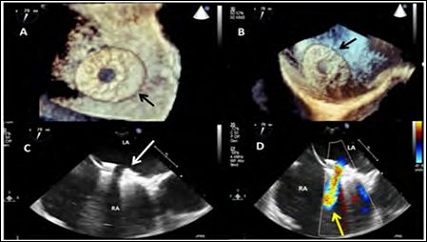

The Atrial Flow Regulator (AFR) device (Occlutech, Helsingborg, Sweden) (Figures 2A and 2B, Supplementary Table 1) with an 8-mm fenestration, 5-mm height and 21-mm discs diameter was implanted into the interatrial septum (Figure 3). Postoperative TEE showed left-to-right interatrial shunting through the device (Figure 4), significantly reduced mitral annular area and trivial residual mitral regurgitation (Figure 5). Post-procedural right heart catheterization demonstrated a drop in PCWP (12 mmHg), an increase in RA and a 1.2 QP/QS ratio (Table 1). At 3-months follow-up the patient was asymptomatic (NYHA I), BNP decreased to 380 ng/L and the 6MWT distance increased to 470 m. TTE showed AFR patency, mild mitral regurgitation (Figure 6, Supplementary Movie 1, B), moderate tricuspid regurgitation with mildly enlarged but normally functioning right ventricle.

Figure 4: A-B: 3D TEE enface views showing the implanted AFR device (black arrow). C-D: TEE two-dimensional color Doppler showing the fenestrated device (white arrow) embedded in the atrial septum and the device patency with a left-to-right shunting (yellow arrow).

Note: RA: Right Atrium; LA: Left Atrium.